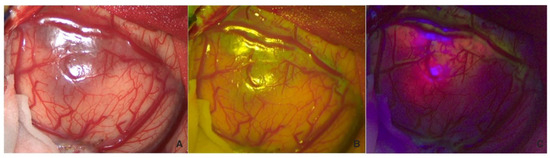

Finally, the margins of the cavity were explored with both fluorophores in sequence to confirm the absence of fluorescent pathological tissue (Figure 3).

Figure 3. Visualization in white light (A), FL 560 (B), and FL 400 (C) of the cavity after complete resection, with no residual tumor visible with any fluorescent dye.